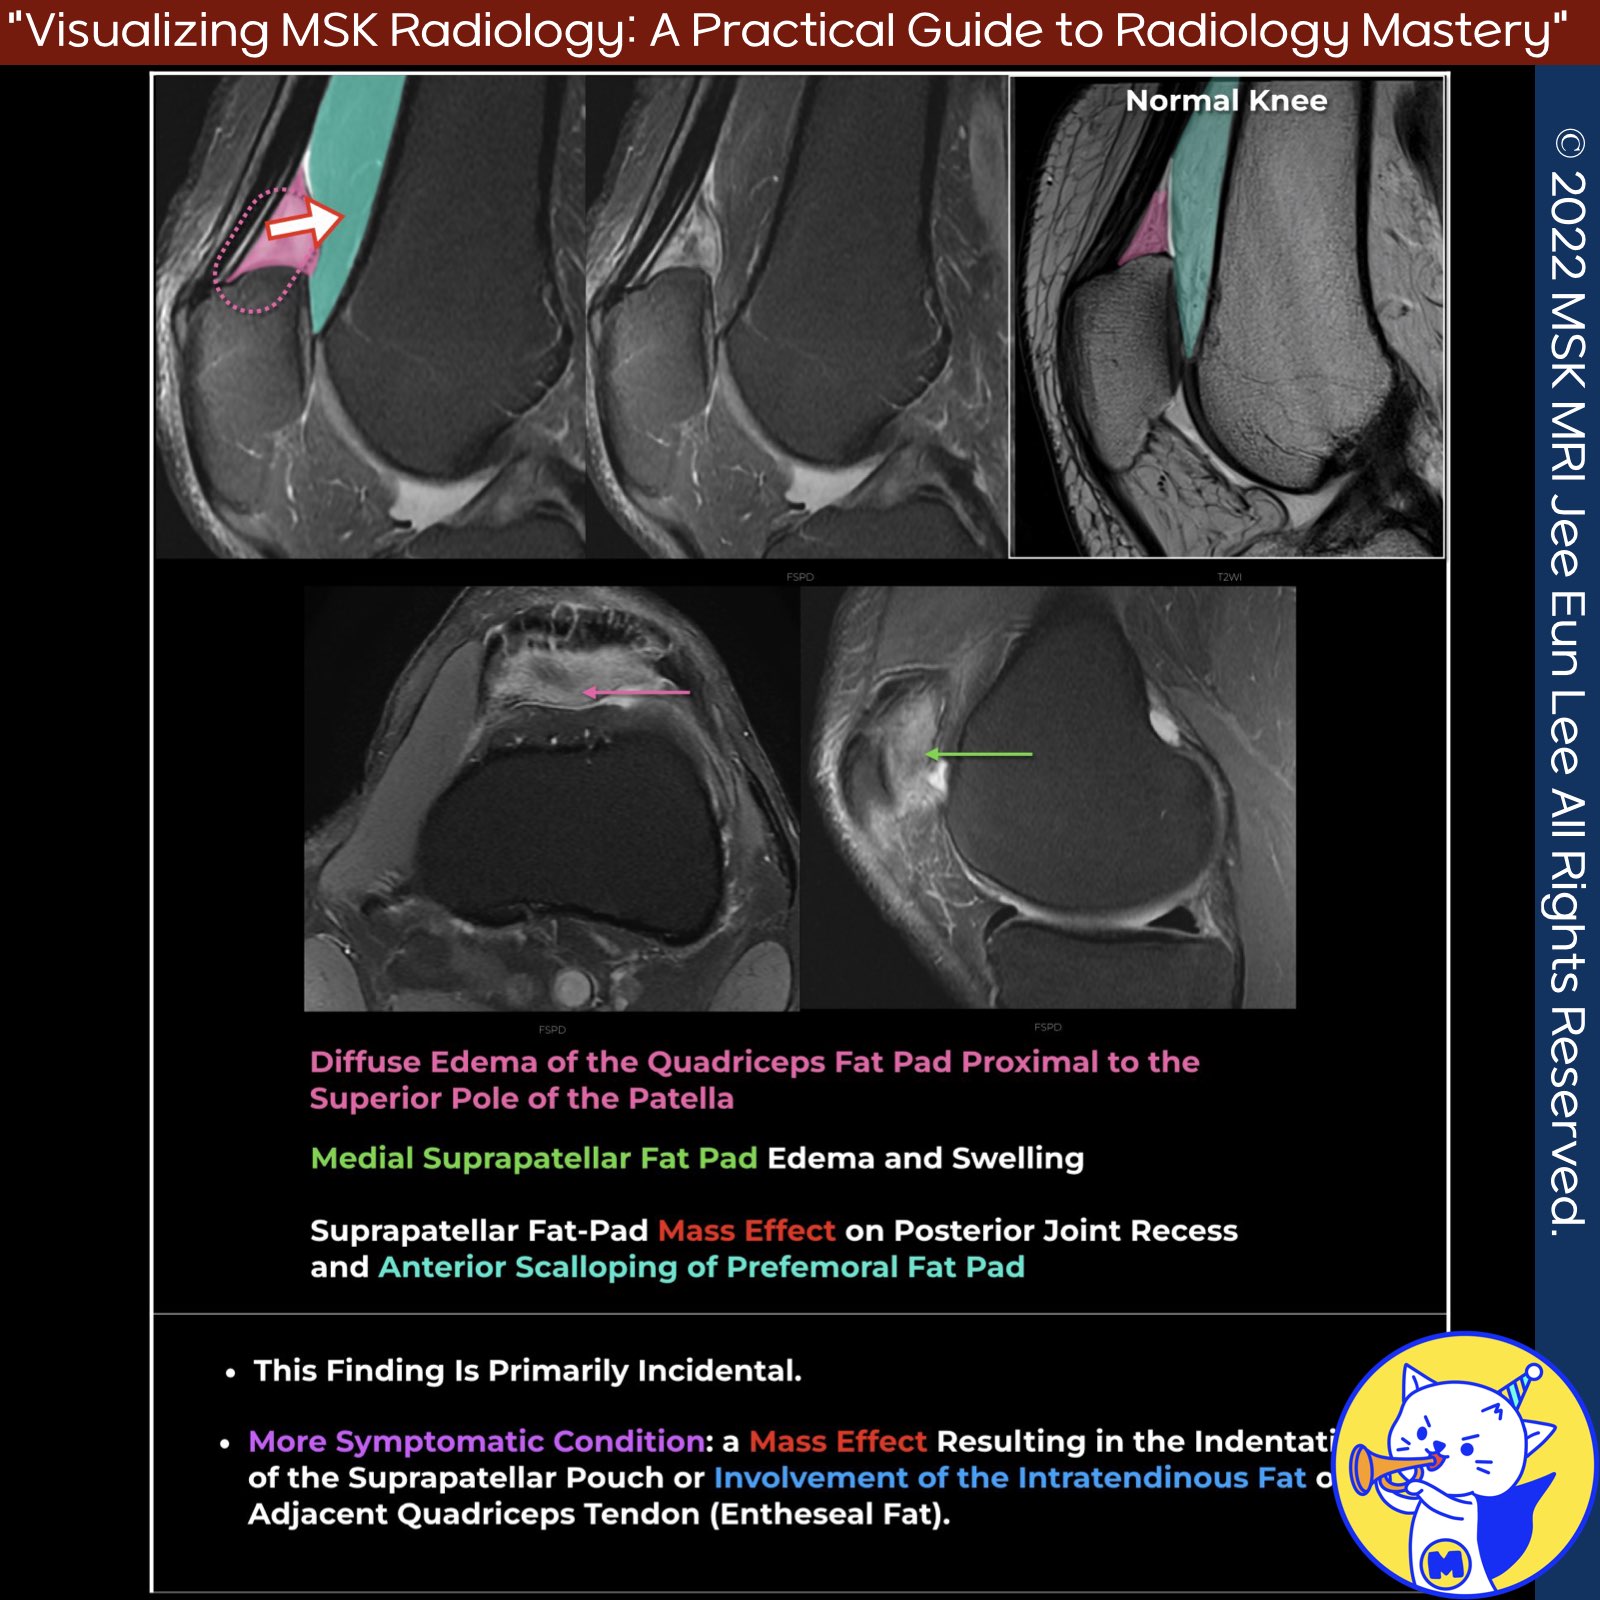

📌 Quadriceps Fat Pad (Anterior Suprapatellar Fat Pad)

- Radiologists should assess the quadriceps fat pad for size, morphology, and signal intensity.

- An abnormal signal on fluid-sensitive MRI is defined as greater than muscle but less than fluid.

- As the signal intensity approaches that of fluid, a mass effect with a posterior convex border is more likely (1).

✅ Common MRI Findings

- High signal intensity deep to the distal portion of the tendon within the quadriceps fat pad is common.

- While often incidental, it can be associated with anterior knee pain when there is a mass effect indenting the suprapatellar pouch (3)).

- High signal intensity on T2-weighted images may indicate an inflammatory cyst within the quadriceps fat pad, necessitating further investigation to understand its impact on knee function (4).

✅ Anatomy of Anterior Suprapatellar (Quadriceps) Fat Pad

- The quadriceps fat pad is a small triangular structure located superior to the patella and deep to the quadriceps tendon.

- It is separated from the prefemoral fat pad by the suprapatellar bursa. This fat pad is believed to promote stress dissipation or act as a mechanosensory organ (1).